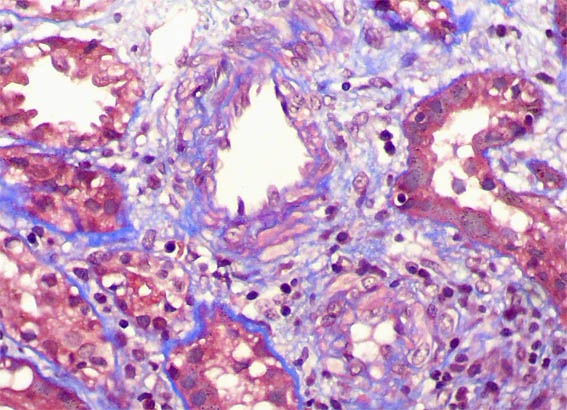

Figura 4. Tricrómico de Masson, X400.